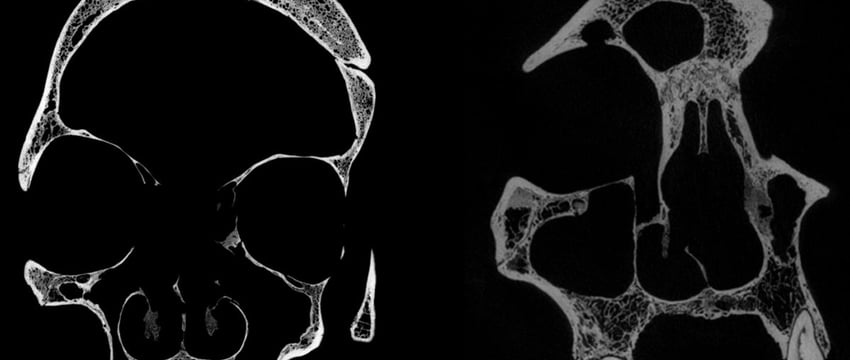

Два черепа - череп и нижняя челюсть 236, датируемые периодом между 2687 и 2345 годами до н. э., принадлежали мужчине в возрасте от 30 до 35 лет, в то время как череп E270, датируемый периодом между 663 и 343 годами до н.э., принадлежал женщине, которая была старше 50 лет.

Микроскопическое исследование черепа 236 показало наличие обширного повреждения, связанного с чрезмерным разрушением тканей, известного как новообразование.

Кроме того, по всему черепу было разбросано около 30 небольших округлых метастазов со следами порезов, вероятно, нанесенных острым предметом, например металлическим инструментом.

Анализ черепа E270 также выявил обширное повреждение, характерное для раковой опухоли, которая привела к разрушению костей, и два повреждения в результате травматических повреждений, после которых было проведено лечение.